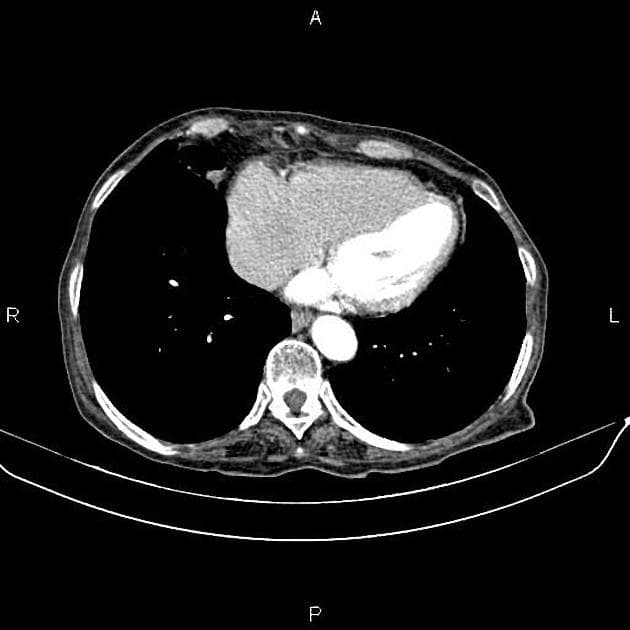

Chẩn đoán & Phát hiện

Thành dạ dày dày không đối xứng và tăng quang mạnh do thâm nhiễm u tại tâm vị và phần gần bờ cong nhỏ, kèm theo nhiều hạch bạch huyết lớn quanh dạ dày. Các hạch bạch huyết lớn này tiếp xúc sát với thùy gan trái và tuyến thượng thận trái, cùng với tình trạng tuyến thượng thận trái lớn nhẹ, gợi ý có sự xâm lấn tại chỗ. Có một hạch bạch huyết lớn nằm ở chuỗi hạch dưới hoành phải. Ngoài ra, có một khối lớn, không đồng nhất với bờ không đều ở gan, biểu hiện tăng quang ngoại vi sớm kèm washout muộn và hoại tử trung tâm rộng. Có tình trạng giãn nhẹ ống mật trong gan ở vùng ngoại vi của khối u. Phần còn lại của gan bình thường và không có dấu hiệu của xơ gan nền. Có một nang kích thước 8 mm ở lách. Một vài nang nhỏ cạnh bể thận được ghi nhận ở cả hai thận, quan sát rõ hơn trên các hình ảnh thì bài tiết. Bệnh nhân đã được thực hiện sinh thiết khối u dạ dày qua nội soi và sinh thiết kim lõi khối u gan dưới hướng dẫn siêu âm. Kết quả giải phẫu bệnh và hóa mô miễn dịch xác nhận ung thư biểu mô tuyến dạng tế bào gan nguyên phát của dạ dày kèm di căn gan. THẢO LUẬN: Trường hợp này minh họa một ca ung thư biểu mô tuyến dạng tế bào gan tiến triển ác tính của dạ dày, xuất phát từ tâm vị và phần gần bờ cong nhỏ ở một bệnh nhân lớn tuổi, biểu hiện với di căn hạch vùng tiến triển và di căn gan lớn, nồng độ AFP huyết thanh cao, cùng các đặc điểm hình ảnh có thể rất giống với ung thư biểu mô tế bào gan nguyên phát. Ung thư biểu mô tuyến dạng tế bào gan của dạ dày là một loại ung thư dạ dày hiếm gặp, có độ ác tính cao, về mặt mô học giống với ung thư biểu mô tế bào gan và thường sản sinh alpha-fetoprotein (AFP). Nó chiếm khoảng 1% các trường hợp ung thư dạ dày và thường được phát hiện ở giai đoạn muộn với di căn gan và di căn hạch. Ung thư biểu mô tế bào gan nguyên phát và ung thư biểu mô tuyến dạng tế bào gan của dạ dày di căn gan có thể có hình thái rất giống nhau; tuy nhiên, chúng khác nhau về bối cảnh lâm sàng, đặc điểm hình thái và hóa mô miễn dịch.